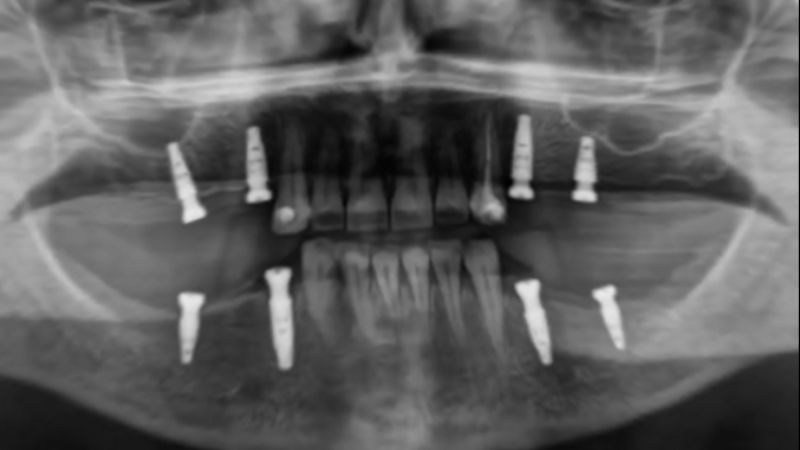

Implantologia

L’implantologia permette di sostituire denti mancanti con protesi fisse, evitando dentiere e ponti, grazie a soluzioni personalizzate e tecnologie avanzate.